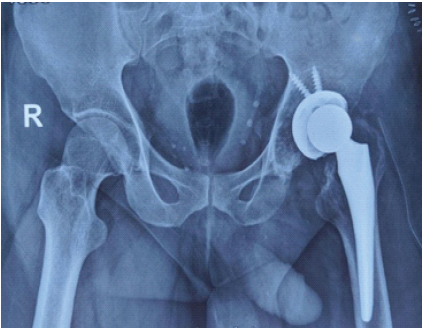

Intraoperative stability was satisfactory. Post-operative radiographs confirmed appropriate alignment and positioning of the prosthetic components (Fig. 5).

Figure 5: Immediate post-operative radiograph.

At the 12-week post-operative review, the patient was permitted to resume full weight-bearing with the aid of crutches and the above-knee prosthetic limb. Follow-up radiographs at 6 months demonstrated satisfactory osseointegration of the implants, with no evidence of component subsidence or osteolysis (Fig. 6). Clinically, the patient remained pain-free on the operated side and was mobilizing independently with crutches and the prosthesis. Functional outcome, as measured by the HHS, improved markedly from a pre-operative score of 30–70 at the latest follow-up.

Figure 6: Follow-up radiograph at 12 weeks.